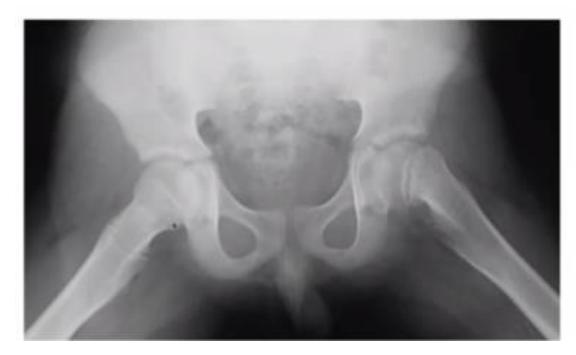

A 13 years old patient, she is known to have idiopathic scoliosis. X-ray pelvis was requested for her.

- 1. Mention the name of the sign seen the X-ray.

- Risser sign

- 2. How it can help in taking decision the management?

- By assessing potential of growth to evaluate potential deformity progression (e.g. scoliosis)

A 15-month-old child was brought to the clinic because of painless limping. There is no history of trauma. The pelvic x-ray is shown.

Q1: Write two abnormalities seen on the X-ray.

- Lateralization of the ossifying centre

- Acetabular angle more than 27ยฐ

- Broken Shenton line

- Shortening of the line from greater trochanter to the horizontal line

Q2: What is the most probable diagnosis?

- Developmental dysplasia of the hip (DDH)